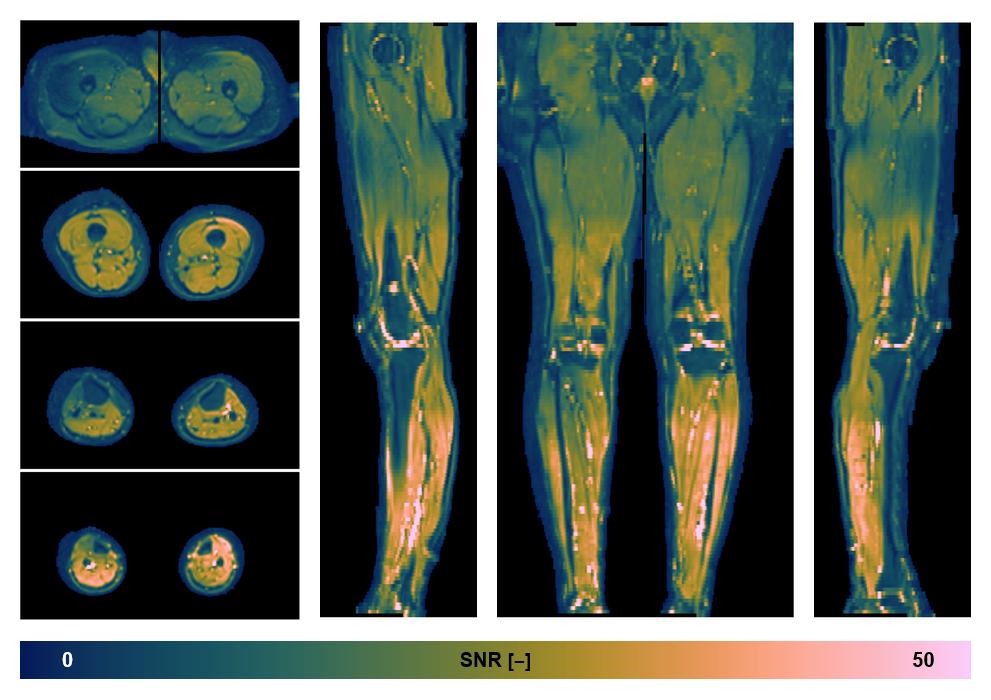

• SNR distribution

The SNR distribution of the dixon data.